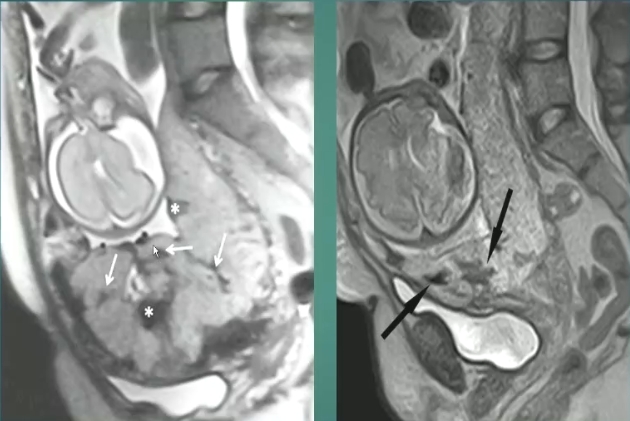

1、胎盘内T2暗带

2、肌层变薄

3、胎盘信号不均质

4、胎盘突出